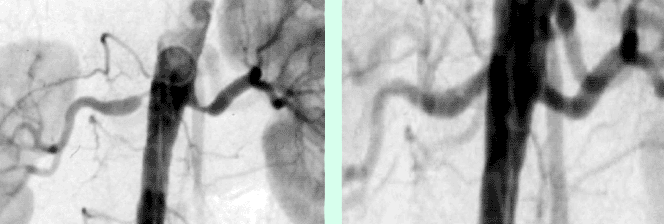

Die Abbildungen A und B zeigen einen 67-jährigen Mann nach Stentimplantation in die linke Arteria carotis interna vor 2 Jahren.

Abb. B zeigt die CT Angiographie des Stents in der linken ACI, welcher regulär entfaltet und perfundiert ist.

Abb. A zeigt jedoch eine höchstgradige Stenose der ACI auf der rechten Seite (Pfeil).